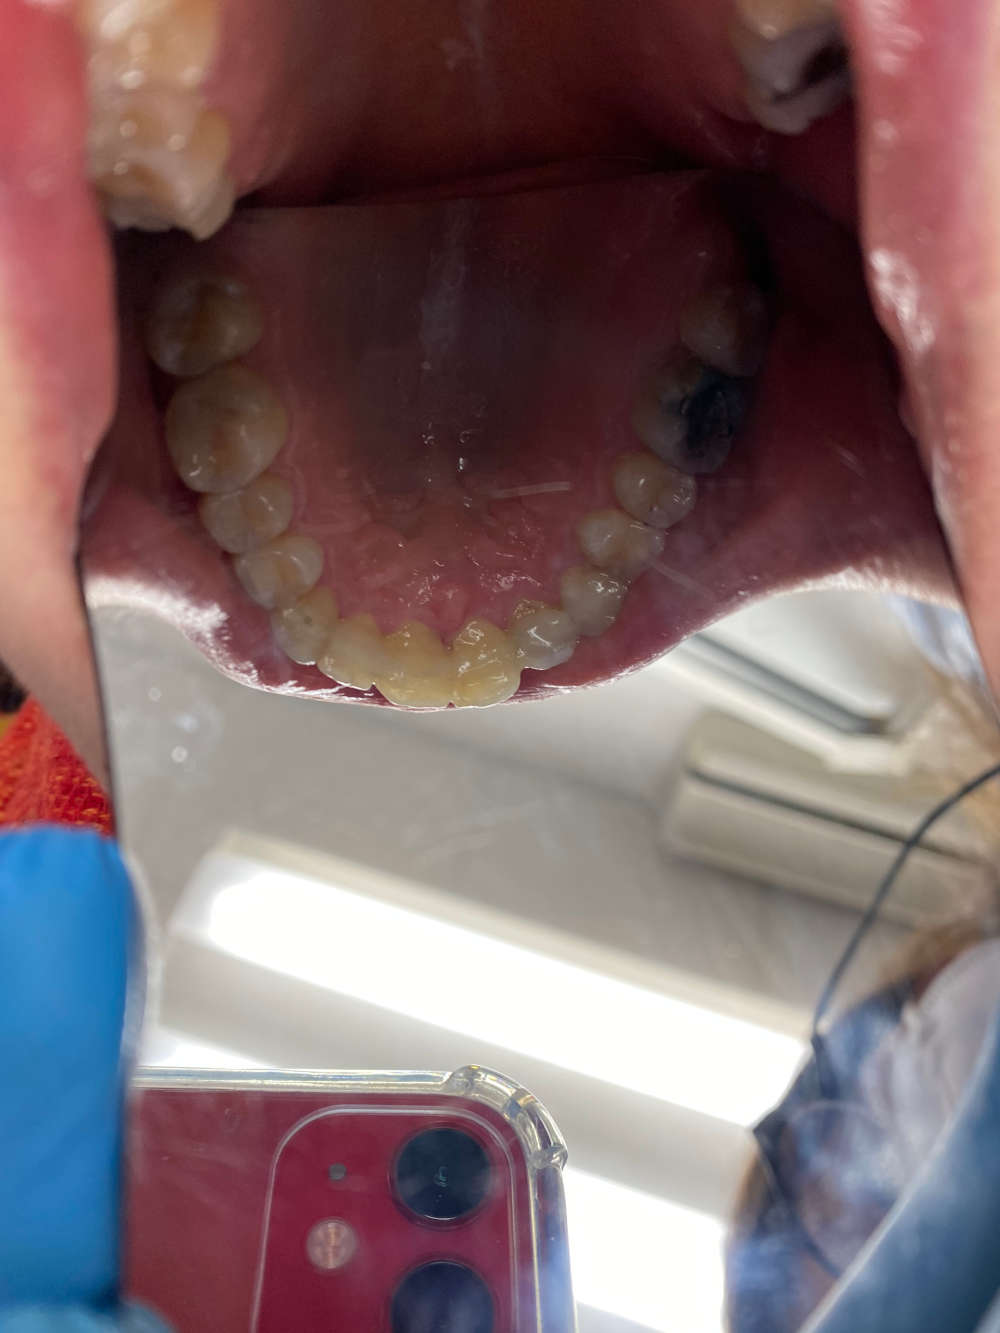

La grande nouveauté est que des gouttières transparentes sont mises en place. Pour une pleine efficacité, il faut être sérieux dans le plan de traitement et porter les gouttières un certain nombre d'heure par jour, selon la prescription du chirurgien-dentiste.